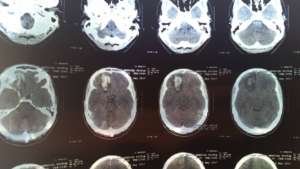

O que aconteceu foi que o baterista Victor Mendonça, sofreu um acidente grave em La Paz, na Bolívia e, sofrendo de um mal súbito, batendo forte com a cabeça contra o chão. Mesmo com isso e ainda com muitas dificuldades, ele cumpriu mais quatro datas (La Paz, Juliaca, Tacna e Arequipa), mas, exames médicos detectaram uma lesão na região frontal do cérebro do exímio baterista e prescreveram repouso absoluto ao mesmo.

Con muchas dificultades, Victor realizó cuatro conciertos (La Paz, Juliaca, Tacna y Arequipa) en condiciones totalmente adversas. Sin embargo, exámenes médicos realizados en Arequipa, Perú, constataron una lesión en la región frontal del cerebro y los médicos locales prescribieron inmediatamente descanso absoluto por tiempo indefinido para evitar el agravamiento de la lesión.

Com muitas dificuldades, Victor realizou mais quatro shows (La Paz, Juliaca, Tacna e Arequipa) em condições totalmente adversas. Todavia, exames médicos realizados em Arequipa, Peru, constataram uma lesão na região frontal do cérebro e os médicos locais prescreveram imediatamente repouso absoluto por tempo indeterminado para evitar o agravamento da contusão.

With great struggle, Victor performed four more shows (La Paz, Juliaca, Tacna and Arequipa) in totally adverse conditions. However, medical examinations in Arequipa, Peru, found an injury to the frontal region of the brain and local doctors immediately prescribed absolute rest indefinitely to avoid worsening the contusion.